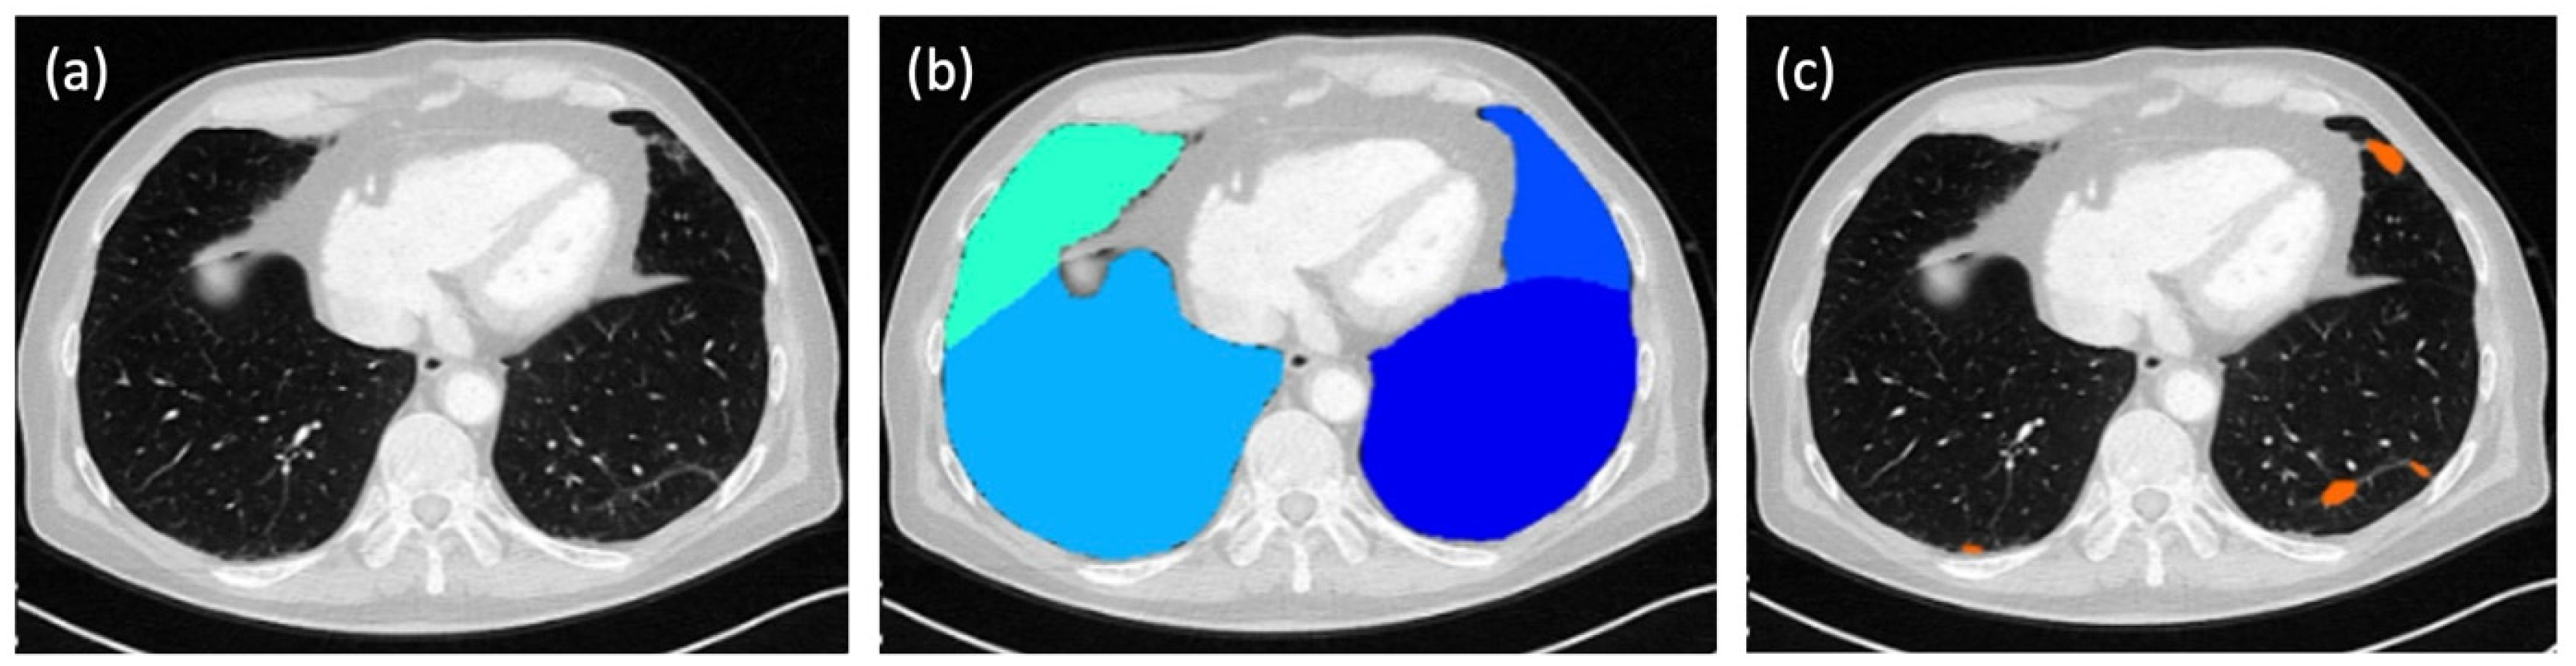

In parallel to the evaluation by the three human readers, the score for each patient was calculated fully automatically by a dedicated, AI-based software tool (ADVANCE chest CT, contextflow GmbH, Vienna, Austria; Figure 1). In this way, four different total scores were available for each patient for comparison.

Figure 1. Fully automated evaluation of a chest CT scan by an AI-based software tool (ADVANCE chest CT, contextflow GmbH, Vienna, Austria): (a) CT image without any software overlays; (b) automated segmentation of the lung lobes (turquoise, middle lobe; light blue, right lower lobe; blue, lingula; dark blue, left lower lobe); (c) AI-generated detection of ground-glass opacities (GGO) in the left lower lobe, the lingula, and the right lower lobe, marked in orange.